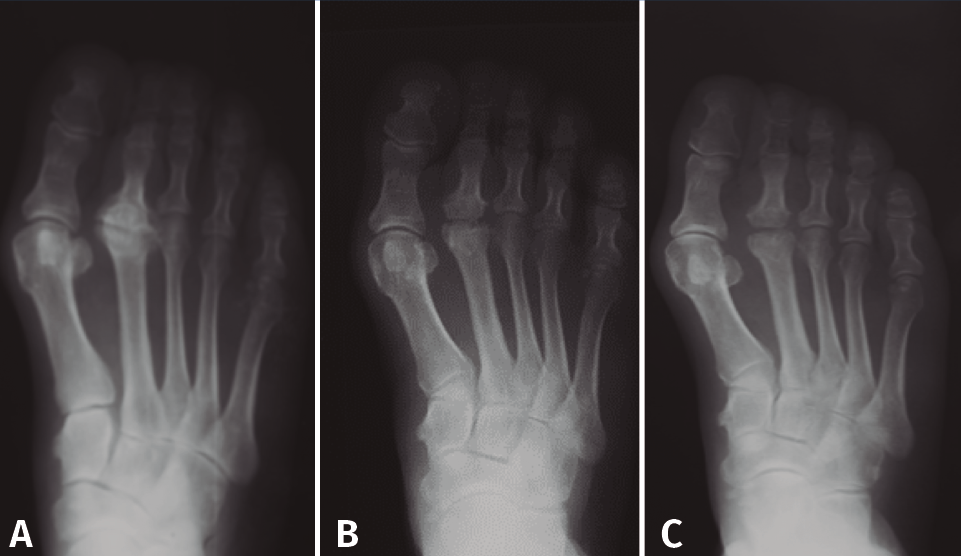

Basándose en la historia natural de la enfermedad y atendiendo a los cambios radiológicos, Smillie(16) clasifica, con propósito terapéutico, la lesión en 5 estadios (Figura 4):

- Estadio 1: aparece una línea de fractura a través de la epífisis.

- Estadio 2: se produce una depresión central de la cabeza por colapso del hueso subcondral. El espacio articular puede ensancharse.

- Estadio 3: la depresión central hace que se proyecten hacia delante los bordes medial y lateral de la cabeza, manteniéndose intacta la parte plantar.

- Estadio 4: la parte central necrosada de la cabeza puede desprenderse de la parte plantar, formándose un cuerpo libre articular.

- Estadio 5: aplanamiento de la cabeza metatarsal y van apareciendo los cambios degenerativos secundarios.

Figura 4. Estadios de Smillie. A: estadio I; B: estadio II; C: estadio III; D: estadio IV; E: estadio V.